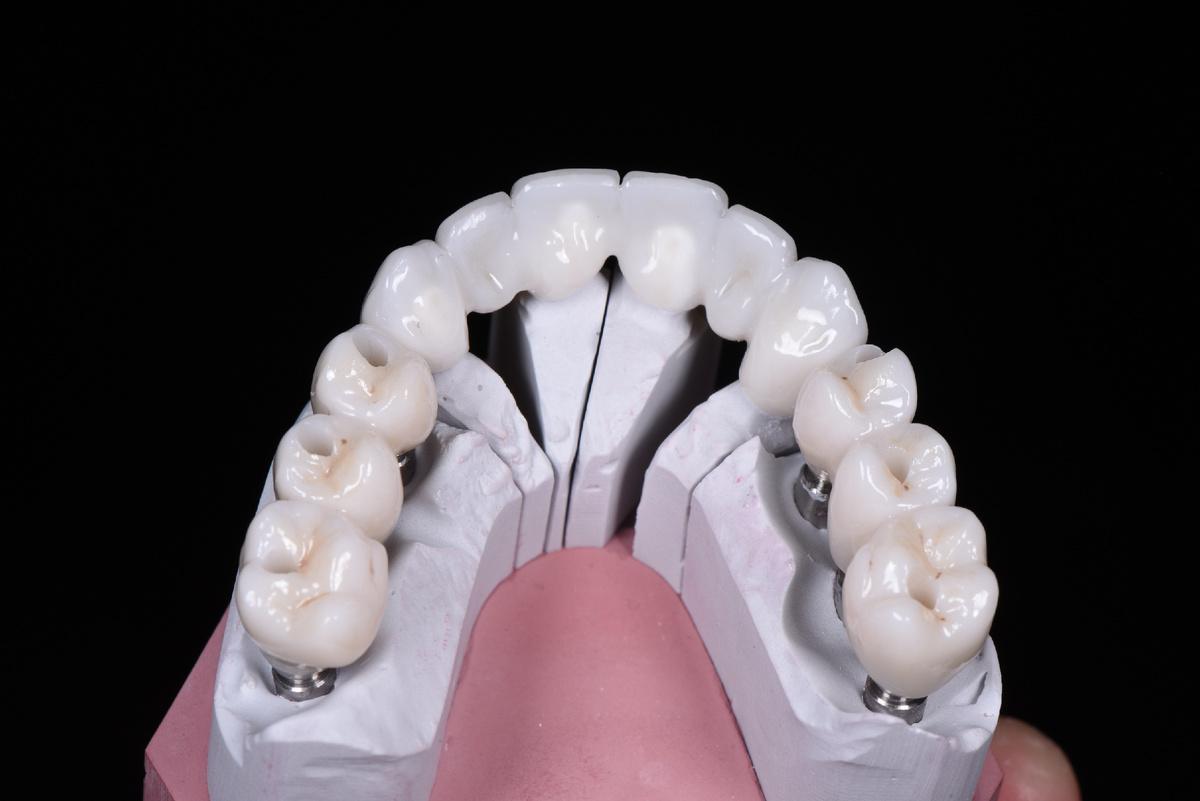

Протезирование

Верхняя челюсть: 2 мостовидных протеза в жевательных отделах с опорой на 3 имплантата и мост на 6 единиц с опорой на 4 собственных зуба

Следующий шаг — коронки на нижние зубы:

Завершающий этап — после протезирования на имплантатах на нижней челюсти слева, в той области, где костная ткань восстанавливалась дольше всего